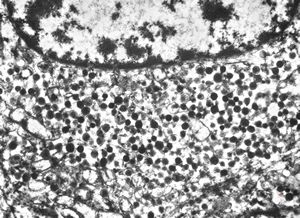

F, 72y. | carcinoid … metastasis to lymphonode